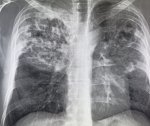

IMG20251016101810.jpg

Где пиздецома?

Аноним 16/10/25 Чтв 08:58:50 #15 №325599636

>>325599617

>>325600080

пизда твоей матушки

Оператор лаборант же, он фоткает я описываю.

Аноним 16/10/25 Чтв 09:20:05 #27 №325600162